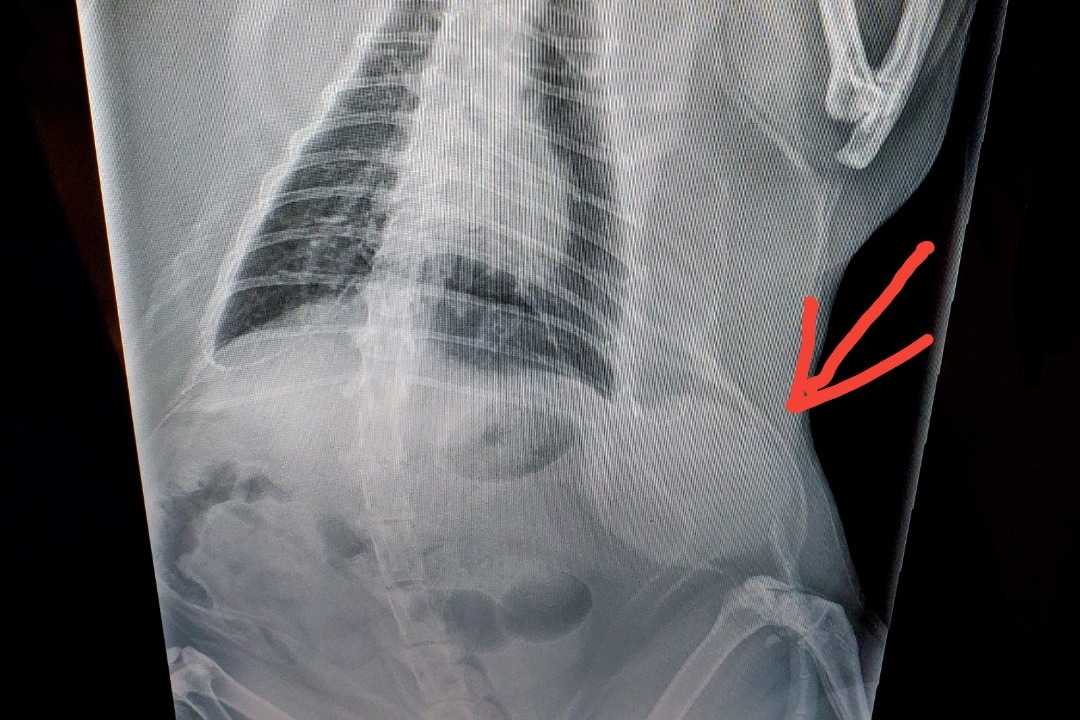

I would like you all to meet marco we rescued him 14 years ago at the age of approximately 3 weeks old after hearing his faint cries for help, he was stuck in a Cinder block. He has brought so much joy into our home.... last month we discovered a lump on the left side of his abdomen. We brought him to the vet and they did an ultrasound and he was diagnosed with soft tissue sarcoma. he has seen numerous vets which pretty much had the same outcome we found a vet on SI that's the most affordable but still out of our budget we would love to give him a second chance, he means the world to us. If you could open your hearts to help even the smallest donation would be appreciated immensely